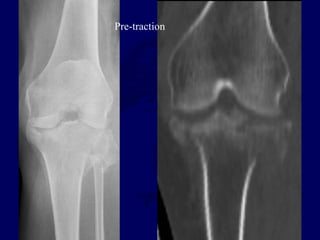

Pre-traction

Post-traction